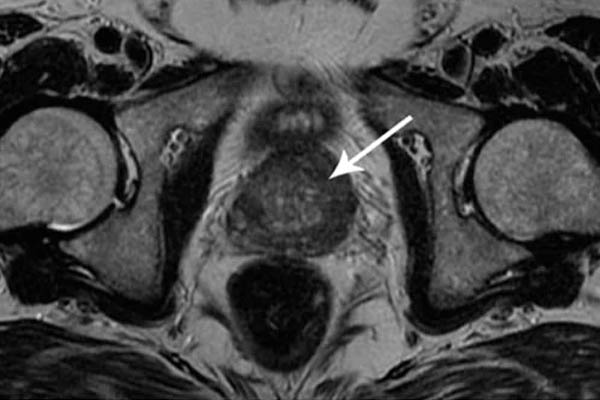

alt_text

Kanker prostat. Ini didiagnosis pada seorang pria berusia 58 tahun. Alasannya adalah penahanan nafsu dalam jangka panjang (dari usia 51). Pria itu meninggal.